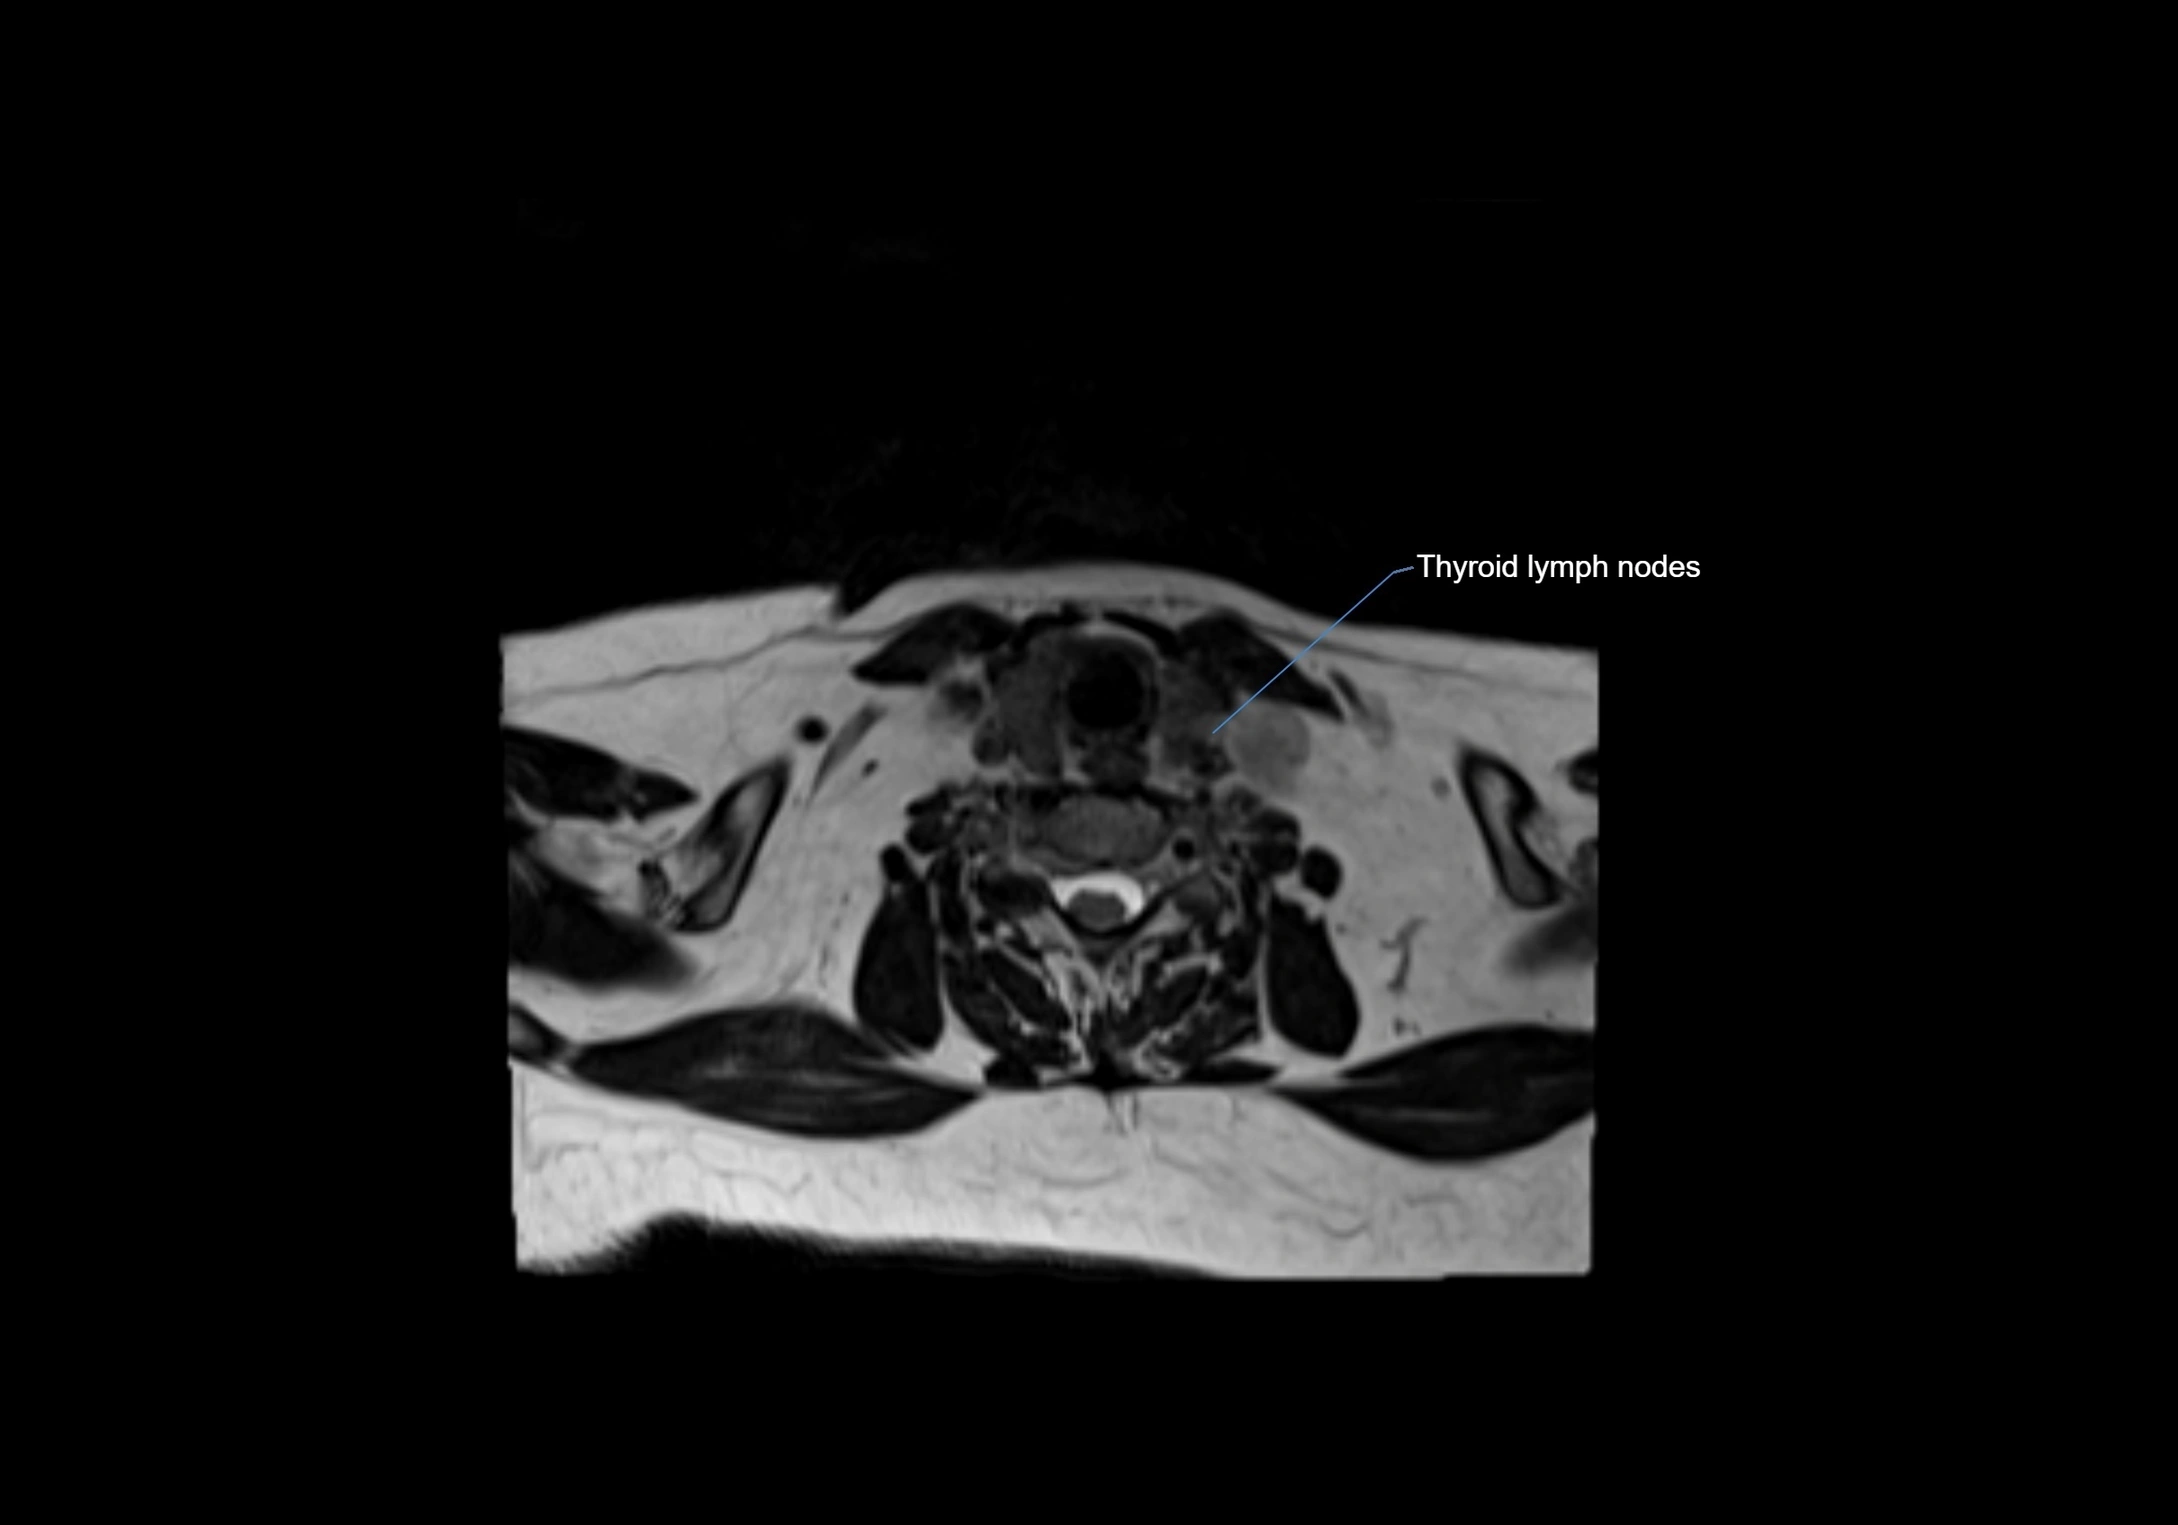

MRI images

image